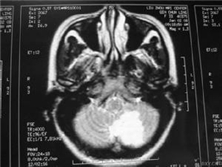

散发性脑炎

散发性脑炎,又称散发性病毒性脑炎、非特异性脑炎和非典型性脑炎。它是神经系统常见的...

脑电图(EEG)